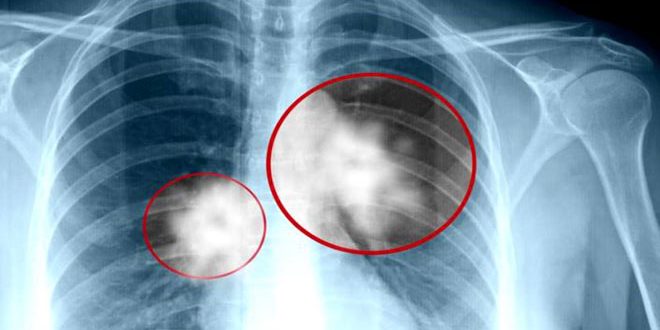

كشف علماء ألمان أن سرطان الرئة القصبي من بين الأورام التي تملك أسوأ فرصة للتعافي وذلك بسبب انتشاره دون وضوح الأعراض.

ونقلت صحيفة فوكس الألمانية عن العلماء قولهم في بحث لهم:”إن سرطان الرئة القصبي ينمو فترة طويلة دون أن يلاحظه أحد ودون أن يسبب إزعاجاً للمريض وينتشر مبكرا خارج الرئتين إلى أعضاء أخرى وهو أكثر عدوانية من سرطان الرئة ذي الخلايا غير الصغيرة الذي ينمو ببطء نسبيًا وغالبًا في مناطق محدودة من الرئة.

ويعاني مرضى سرطان الرئة القصبي السعال وآلاما في الصدر وفقدان الوزن السريع والالتهاب الرئوي المستمر أو التهاب القصبات وعادة ما تنشأ الأورام الخبيثة من الخلايا المخاطية في الشعب الهوائية بالجهازالتنفسي.